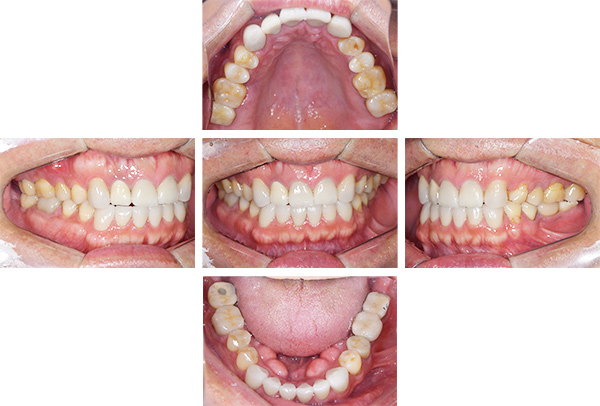

インレー症例

治療前

治療後

治療期間 8回(2ヶ月)

費用 ・セラミックインレー9本

合計:495,000円

治療リスク・副作用 ・詰め物、被せ物をする時は自分の歯を削ることになります

・歯ぎしり・食いしばりが強い方は、セラミックが割れてしまうことがあります。